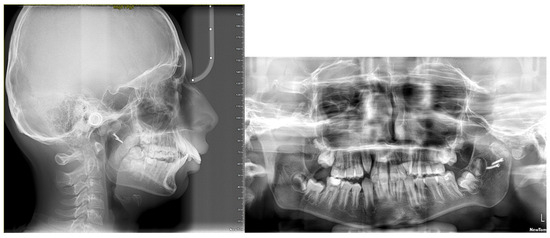

The panoramic radiograph showed the gap arthroplasty performed by the second author (SU) on the left TMJ (Figure 2). The second and third molars and upper right canine were all developing.

Figure 2.

Pre-treatment lateral cephalogram and panoramic radiograph.

The lateral cephalometric findings (Figure 2 and Table 1) confirmed a retrognathic mandible (SNB = 72.7°, Pogonion to McNamara Nasion Perpendicular = −11.6 mm), proclined maxillary incisors (U1-SN = 114.9°, U1-NA = 31.9°/7.0 mm), and a skeletal Class II malocclusion with an ANB of 10.3° and Wits of 15.8 mm. The patient had a hypodivergent skeletal pattern (SN-GoGn = 22.2°). The maxillary-mandibular planes angle was decreased (19.0°) and showed a short lower anterior face height. The soft tissue analysis revealed protrusive upper and lower lips with an obtuse nasolabial angle (Table 1).